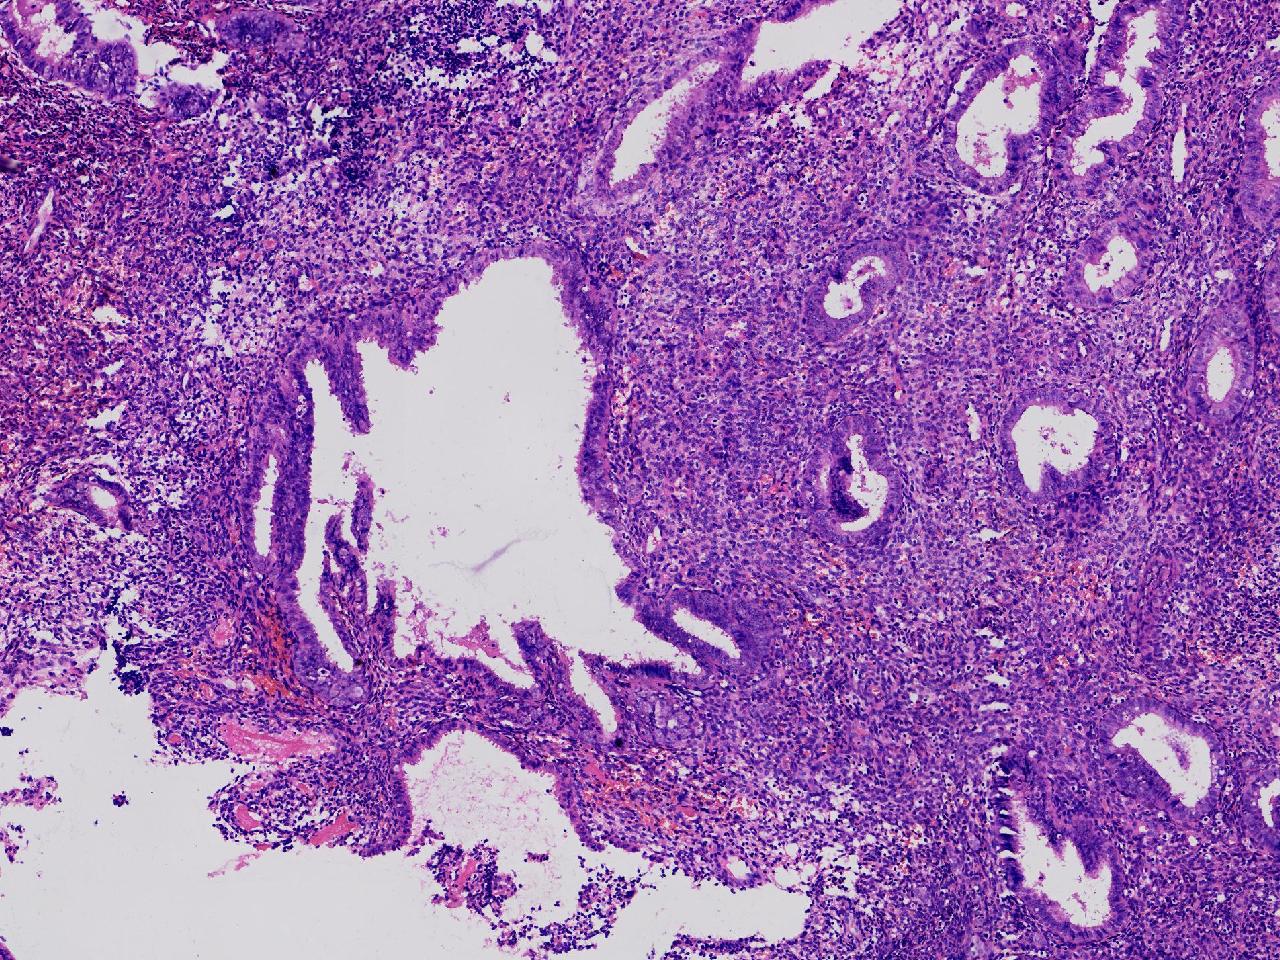

请教诊断。局灶够不够非典?

阴道不规则出血20余日,彩超示:内膜线居中,厚15毫米。

子宫内膜

灰粉色不整形软组织多块,3X2X1厘米。

不够非典

有输卵管上皮化生,感觉不够非典。